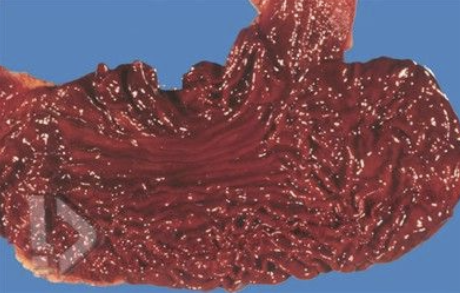

brick-red, large edema fluid, white hemorrhagic foam in trachea, subpleural hemorrhages (paltauf’s spots)

List the expected gross findings associated with drowning.